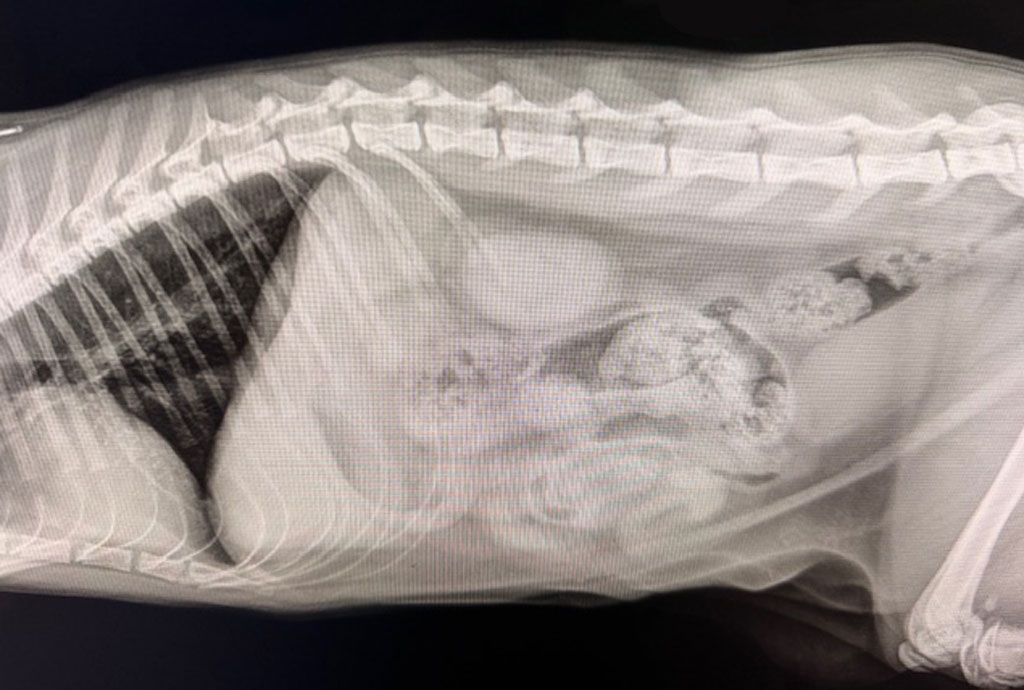

X-rays (radiographs) are one of the most widely used imaging tools in veterinary medicine. They use a small, safe amount of radiation to capture images of the body’s internal structures. Because bone and other dense tissues absorb radiation differently than soft tissues, x-rays are especially useful for:

X-rays produce a quick overall snapshot, making them ideal for first-line diagnostic questions, especially those involving bones, the chest, or acute injuries.